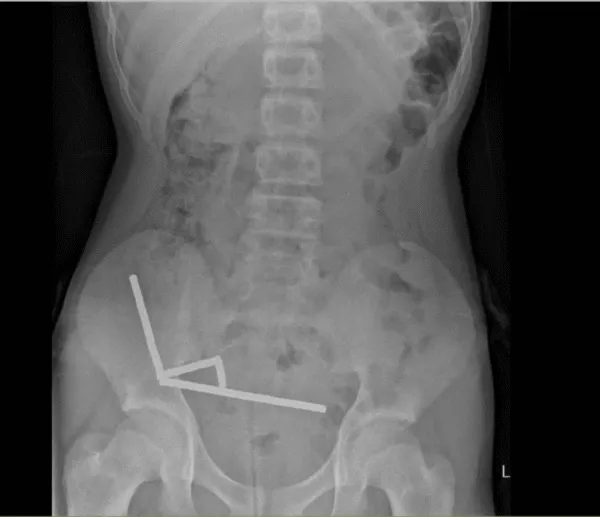

医生通过 X光片观察到,男孩肠道的不同部位出现了四条线状的磁铁链。

腹部 X光片显示了磁铁分布情况来源:Lekamalage et al.,NZMJ,2025

200颗磁铁在患儿腹中形成了磁铁链。来源:Lekamalage et al.,NZMJ,2025